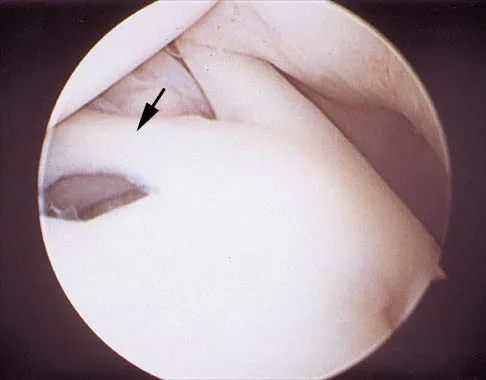

A 24-year-old athlete has a painful right shoulder. Figure 30 shows an intra-articular photograph that was obtained through a posterior portal during arthroscopy; the labrum is indicated by the arrow. Based on these findings, management should consist of

Explanation

A 24-year-old athlete has a painful right shoulder. Figure 30 shows an intra-articular photograph that was obtained through a posterior portal during arthroscopy; the labrum is indicated by the arrow. Based on these findings, management should consist of

Explanation